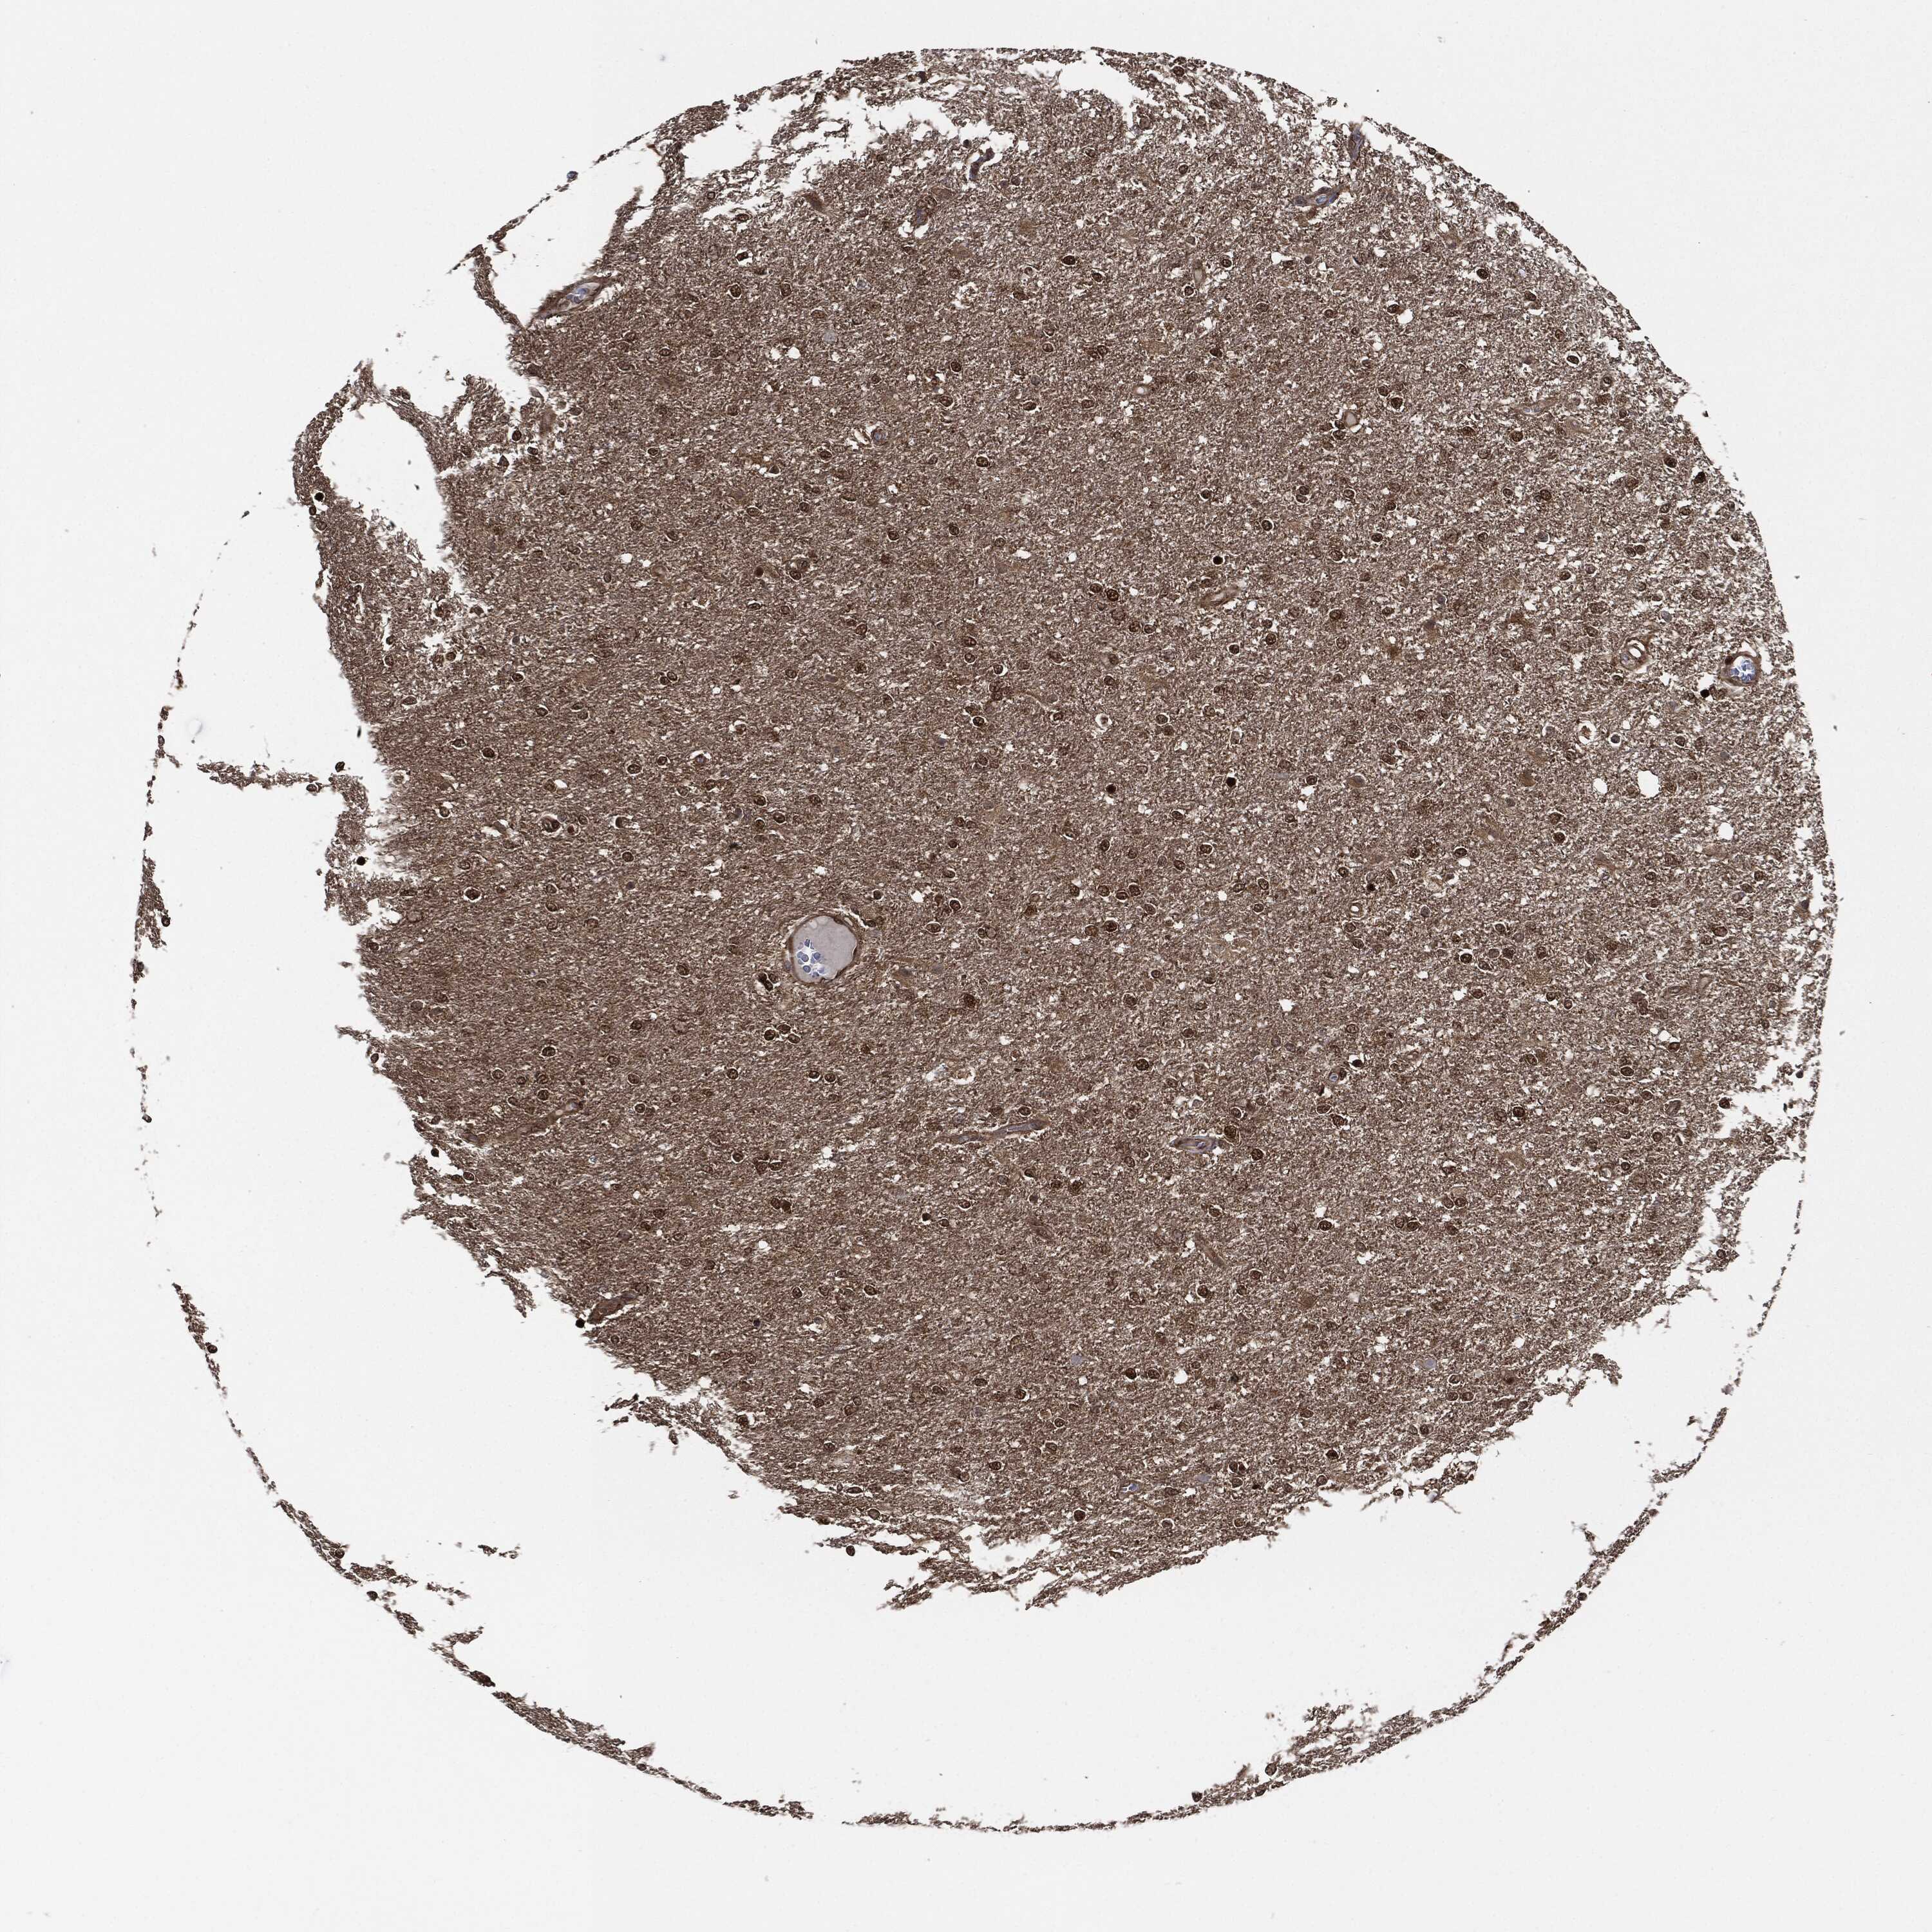

GLIOMA - Protein expressioni

A mouse-over function shows sample information and annotation data. Click on an image to view it in a full screen mode. Samples can be filtered based on level of antibody staining by selecting one or several of the following categories: high, medium, low and not detected. The assay and annotation is described here.

Note that samples used for immunohistochemistry by the Human Protein Atlas do not correspond to samples in the TCGA dataset.

Antibody stainingi

Antibody staining in the annotated cell types in the current human tissue is reported as not detected, low, medium, or high, based on conventional immunohistochemistry profiling in selected tissues. This score is based on the combination of the staining intensity and fraction of stained cells.

Each image is clickable and will lead to virtual microscopy that enables deeper exploration of all samples and also displays staining intensity scores, fraction scores and subcellular localization as well as patient and tissue information for each sample.

Antibody HPA034635

Antibody HPA069977

Antibody HPA071875

Antibody CAB009108

Staining

High

Medium

Low

Not detected

Intensity

Strong

Moderate

Weak

Negative

Quantity

>75%

75%-25%

<25%

None

Location

Nuclear

Cytoplasmic/membranous

Cytoplasmic/membranous,nuclear

Glioma, malignant, Low grade

Glioma, malignant, High grade